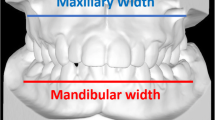

Dento-skeletal measurements were performed on the coronal cross-sections of the CBCT scans by passing through the center of the maxillary and mandibular primary first molar crown in accordance to Miner et al. [33] (Fig. 2). Further, an evaluation of the slices around the permanent upper first molar was often necessary to analyze the inclination of the mesio-buccal root long axis. Dental parameters relative to the width of the second permanent molars and the inclination of the central incisor were also evaluated. Moreover, the change in the palatal depth after both the expansion protocols was assessed according to Bruder et al. [34] (Fig. 2).

The CBCT axial cross section was used to measure the upper and lower arch perimeter before(T1) and after(T2) maxillary expansion (Fig. 3).